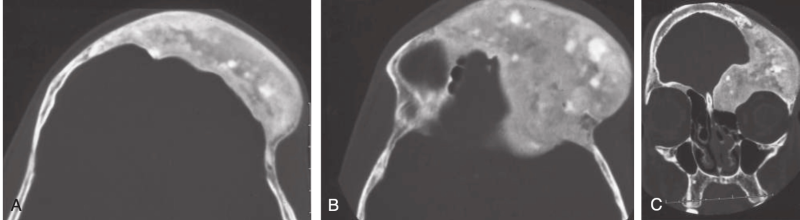

Fibrous dysplasia involving the frontal bone (A) and the superior orbital rim (B) and extending on the floor of the anterior fossa (C), with some compression of the orbit. Note the multiple densities within this bone, as well as some porous changes, especially on the coronal image. This appearance illustrates the vascular nature of these hypersclerotic medullary bone–like lesions.